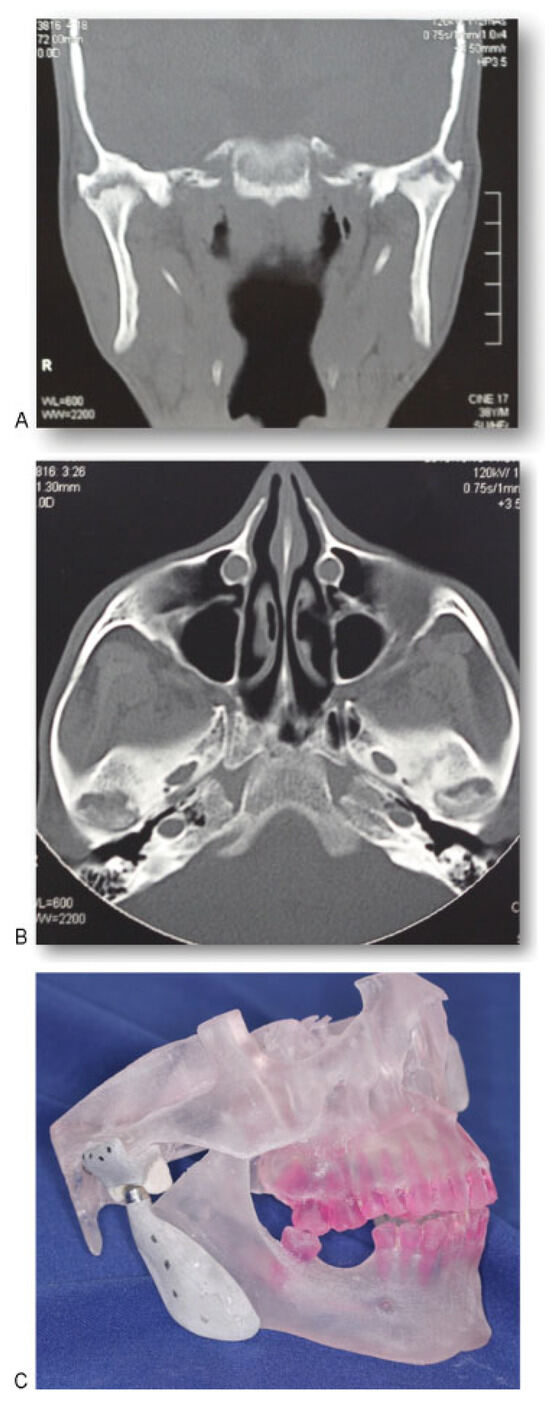

A 38-year-old man with AS was referred to the division of Oral and Maxillofacial Surgery of Piracicaba Dental School for limitation of mouth opening 16 months ago. Examination revealed that he had a 9 mm interincisal opening (Figure 1), with no lateral or protrusive mandibular movements, including severe rigidity of the cervical, thoracic, and lumbar spine. The patient reported that he underwent surgery on both shoulders in 2006 due to the joint involvement caused by the disease. In 2008, the AS affected the right iliac-femoral joint, and the patient had a femoral prosthesis inserted. The same occurred the following year with the left iliac-femoral joint. Computed tomography (CT) of both TMJs confirmed severe ankylosis (Figure 2A,B). Because of the extent of his disease, resection of the ankylotic mass and replacement of both TMJs by total alloplastic joint was indicated [9]. A stereolithographic prototype was built from the CT sections and a mock surgery was done on the prototype for fabrication of individualized prostheses (Figure 2C). The mandibular component is made of titanium, with the condylar head of cobalt–chromium–molybdenum alloy. The fossa component is designed to replace the articulating surface of the TMJ comprised by the glenoid fossa and the articular eminence. It is made of ultra-high molecular weight polyethylene. Its spherical radius allows excellent articulation to the spherical head of the mandibular component. We decided to use a customized prosthesis because it is easier to adapt at the mandibular ramus, eliminating adjustments; the occlusion is better achieved; the length of the surgery is smaller and, consequently, the morbidity and postoperative pain are reduced. Because of the rigidity of his cervical spine and limitation of mouth opening, the induction of general anesthesia was performed by fiberoptic nasoendoscopy. During the surgery, a bodily tilt of the operating table by 20 degrees on each side was required due to the rigidity of his cervical spine. Surgical access was through bilateral preauricular and submandibular incisions. Via the preauricular approach, the affected condyle was removed, the glenoid fossa was smoothed, and the articular component of the prostheses was inserted (Figure 3A,B). From the submandibular incision, the coronoid process was removed and the condylar implant inserted. The same operative sequence was done on the opposite side (Figure 4A,B). Postoperative CT confirmed correct placement of the total joint prostheses (Figure 5A,B). Wooden spatulas and a Therabite (Atos Medical, West Allis, WI) appliance were used for postoperative physiotherapy, and interincisal distance has been maintained at 20 mm at 1-year follow-up (Figure 6).

Figure 5. (A) Postoperative computed tomography (CT) showed the total joint prostheses in the right position—axial view. (B) Postoperative CT showed the total joint prostheses in the right position—coronal view.